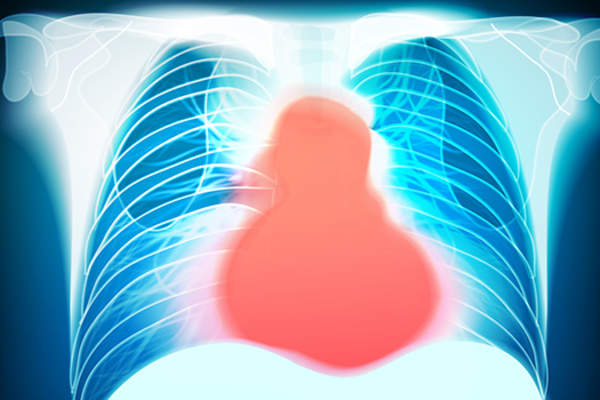

心绞痛是什么感觉

患者和医生经常说,心绞痛感觉上胸部周围有挤压或压力。然而,这并不总是一个足够清晰的画面。其他一些关键心绞痛的说明疼痛:

- 朝后面或辐射武器

- 横跨胸部中部

- 是漫(未在仅一个斑点)

更具体地讲,心绞痛持续时间超过只需几分钟。疼痛不随位置的变化(如坐或躺)改善,疼痛与运动恶化。一些,但不是所有的人经历疼痛放射至下颌或背部,太。可与心绞痛发生的其他症状包括呼吸急促,出汗,恶心,突然疲劳。